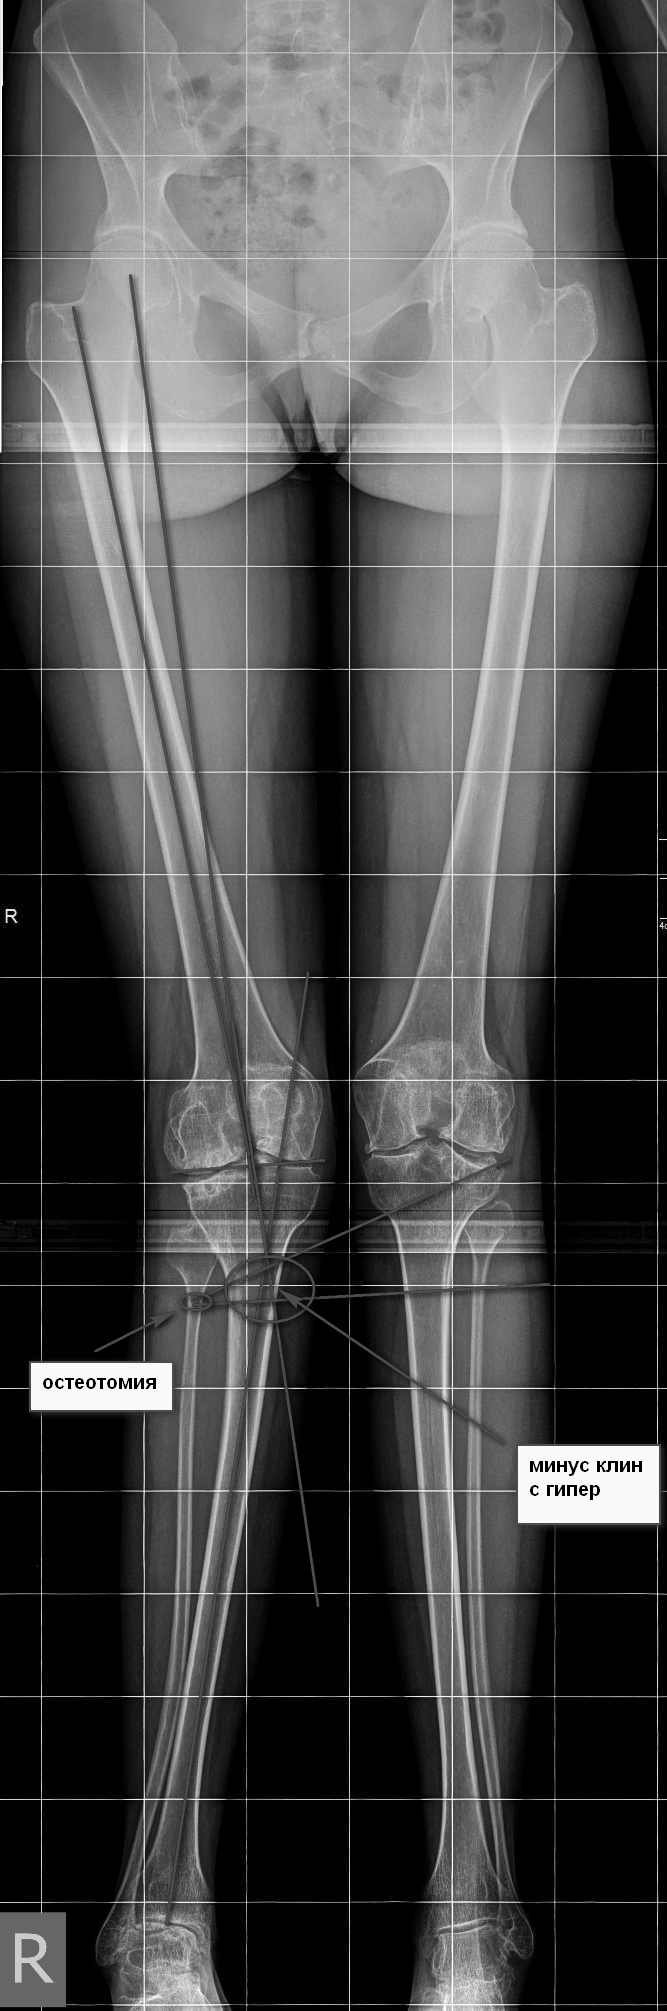

девушка 29 лет с ревматоидным артритом, социальная, лечение получает. вальгусную деформацию на уровне коленных суставов замечает около 10 лет, прогрессирует. Движения в правом коленном суставе:разгибание полное, сгибание около 95-100 град. Боли особой нет. Консультировалась в нескольких НИИ, рекомендовали эндопротезирование.У меня есть желание (вполне, возможно, что и глупое) за сустав "побороться", учитывая возраст, да и первичное протезирование будет не слишком простым. Может исправить деформацию, а там куда кривая судьбы заведет? больше беспокоит боль в голеностопе. В связи с этим есть несколько вопросов: 1. имеет смысл с этим заморачиваться? 2. если да, то в каком объеме? 3. может имеет смысл сделать коррекцию ниже метафиза с одномоментной фиксацией "приличным"гвоздем? Схема прилагается 4. насколько стоит опасаться тракционной нейропатии, стоит сделать острое укорочение или тянуть аппаратом? 5 . еще ряд вопросов, которые я не учел PS книгa Dror Paley пока утеряна вместе с жестким диском, потому не судите строго за дилетанство и приветствуются ваши схемы. Всем большое спасибо за понимание.

Сделаете остеотомию большеберцовой - стопа, которая уже приспособилась к нынешнему положению, повернется кнутри и может утратить контакт с опорой. Голеностопный сустав с признаками выраженной артропатии, скорее всего тугоподвижный. Приспособиться к новому положению не сможет. Значит нужно сразу продумывать последовательность действий, включающую надлодыжечную остеотомию голени или артродез голеностопного сустава (Вам проще оценить его функцию, только по снимку не скажешь). Тем более Вы пишете, что больше беспокоит голеностопный сустав. В этом случае, особенно если думать о надлодыжечной остеотомии, гвоздь может не подойти. А для остеотомий есть хорошие пластины и отработанные техники. С другой стороны, подобное вмешательство можно разбить и на два этапа. Потому что рассчитать все сразу очень сложно. Например, сначала сделать проксимальную остеотомию. Посмотреть, где оказалась стопа и после этого выровнять ее. Но и в этом случае фиксация гвоздем не лучшее решение. Если только не ухитритесь все сделать на одном гвозде. В следующий раз пришлю снимки похожего случая, который делал в 2 этапа.

Максим. Если бы мы вдруг захотели это делать, то остеотомия была бы высокая (над бугристостью). Малоберцовка остаётся интактной. Правда на гвозде не закрепить, но есть пластины

Какую бы не выбрали остеотомию. Выводить ось в ноль я бы не стал. Ориентиром может быть наклон щели голнностопа.

Если пока еще перевариваете, то обдумайте и вариант аппаратного лечения. Все-таки рассчитать все точно под пластину сложно, а аппарат дает возможность внести коррекцию по ходу, уже увидев что куда смотрит под нагрузкой.